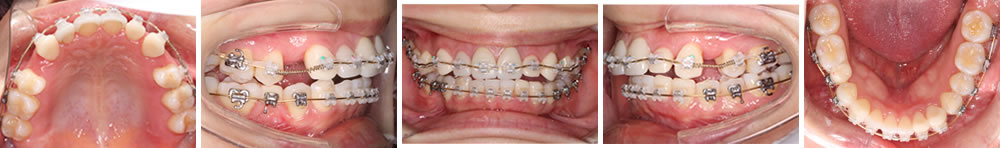

初診時の口腔内

初診時の口腔内写真とレントゲン写真です。上顎左右4番と右下5番が抜歯されています。

顎の拡大が終了し、ワイヤー矯正を開始。失った歯のスペースを確保しながら、舌を邪魔しないような噛み合わせを構築していきます。

インプラント治療終了直前で仮歯を装着した状態の口腔内写真とレントゲン写真です。